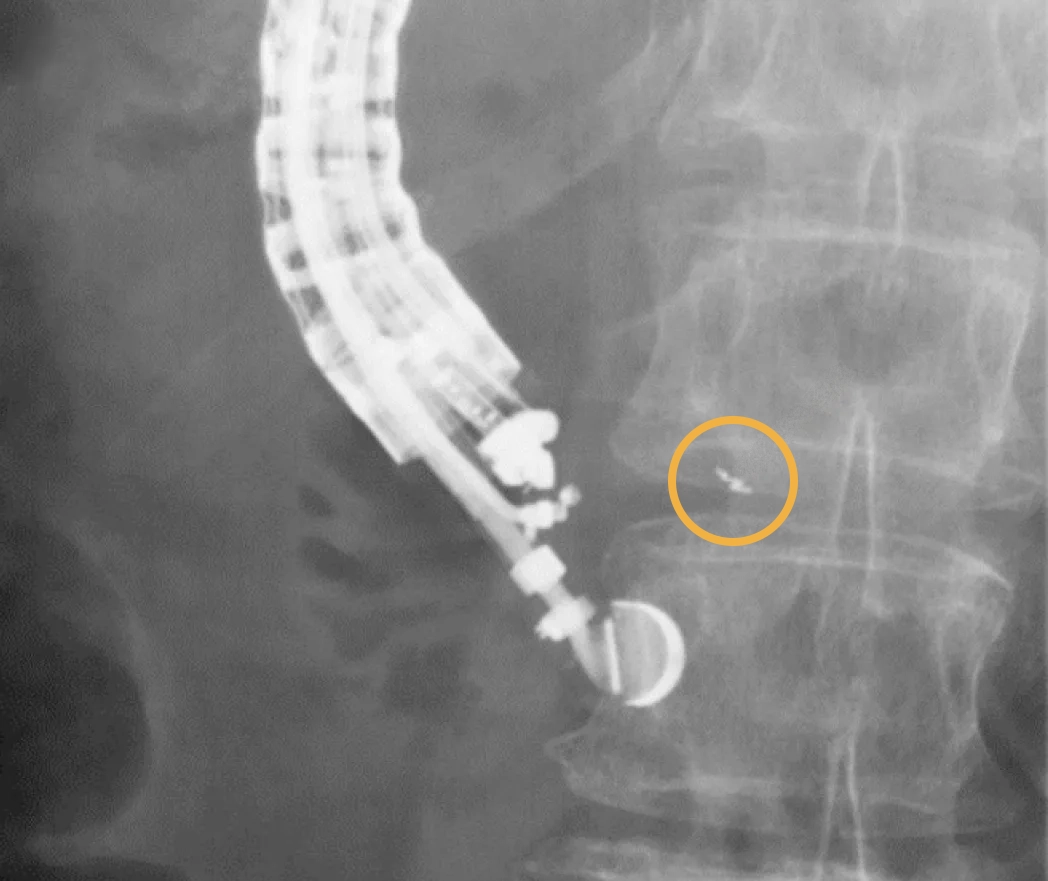

The image shows a 0.28×10 mm Gold Anchor marker implanted in pancreas.

Image courtesy of Reiko Ashida, MD, PhD, FASGE, Co-Director, Departments of Cancer Survey and Gastrointestinal Oncology, Osaka International Cancer Institute, Japan.